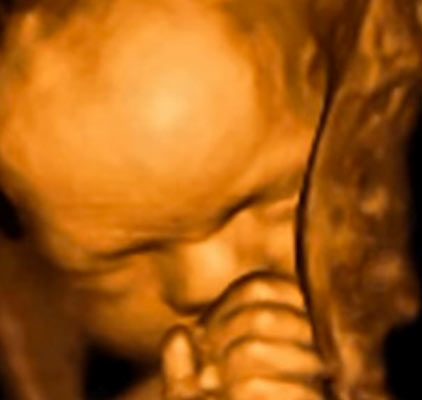

For all expectant parents out there, you can now see your unborn baby in 5D HD Live 4D motion! Miracle View Ultrasound uses brand new cutting edge 3D 4D with 5D HD Live Ultrasound technology to bring images of your unborn baby to life. You can actually see what your baby is going to look like before birth! z

Miracle View Ultrasound is a full service prenatal imaging center offering elective prenatal Ultrasounds. 3D & 4D Ultrasounds can provide a positive bonding experience between the entire family and the unborn baby. Using the same safe ultrasonic sound waves as used in your doctor's office, our HD 5D ultrasound equipment provides a resolution and clarity unsurpassed in the industry. We feel that realistic surface images provide a connection between parents and child that can be beneficial to the whole family. Something special happens to parents when the 3D & 4D 5D HD images are seen compared to the 2D or old 3D/4D images image because the picture of the baby is more realistic.

With the state-of-the-art GE Voluson E8 Expert with HD Live Ultrasound machine, activities of the baby inside the womb can be seen which are difficult or impossible to identify on 2D scanning. With HD 5D scanning the fetus can now be seen to yawn, cry, swallow, blink and perform intricate movements.